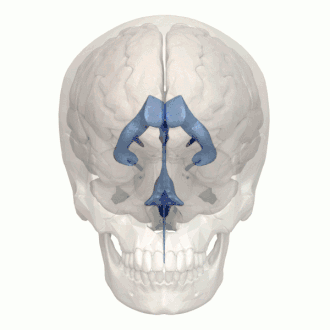

Rotating 3D rendering of the four ventricles and connections

3D rendering of ventricles (lateral and anterior views)

The system comprises four ventricles:[5]

Ventricles

The four cavities of the human brain are called ventricles.[6] The two largest are the lateral ventricles in the cerebrum, the third ventricle is in the diencephalon of the forebrain between the right and left thalamus, and the fourth ventricle is located at the back of the pons and upper half of the medulla oblongata of the hindbrain. The ventricles are concerned with the production and circulation of cerebrospinal fluid.[7]